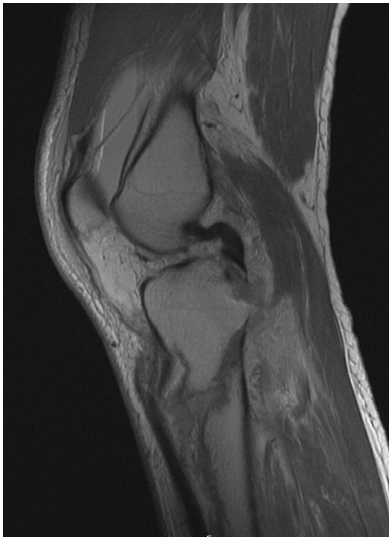

At presentation 1 week after injury, the patient was neurovascularly intact with resolving fracture blisters. The external fixator pin sites showed no evidence of infection. Radiographs showed a complex, largely extra-articular, proximal tibia fracture with dissociation of the tibial tubercle (Fig. 1). Subtle findings of a proximal lateral tibia avulsion fracture (a Segond fracture) and tibial spine comminution raised suspicion for ligamentous knee instability. Diastasis of the proximal fibula from the tibia demonstrated the high energy nature of the trauma. A computed tomography (CT) scan showed the complex proximal tibia fracture with a separate tibial tubercle fragment and confirmed a posterior cruciate ligament (PCL) avulsion fracture and lateral proximal tibia avulsion (Fig. 2). Magnetic resonance imaging (MRI) confirmed a lateral meniscal root tear, disruption of the PCL, proximal tibiofibular capsular ligaments, and moderate posterolateral corner injury (Fig. 3).

Figure 3: MRI shows a secondary deformity of the PCL due to avulsion of the PCL footprint, with a slightly displaced footprint fracture.